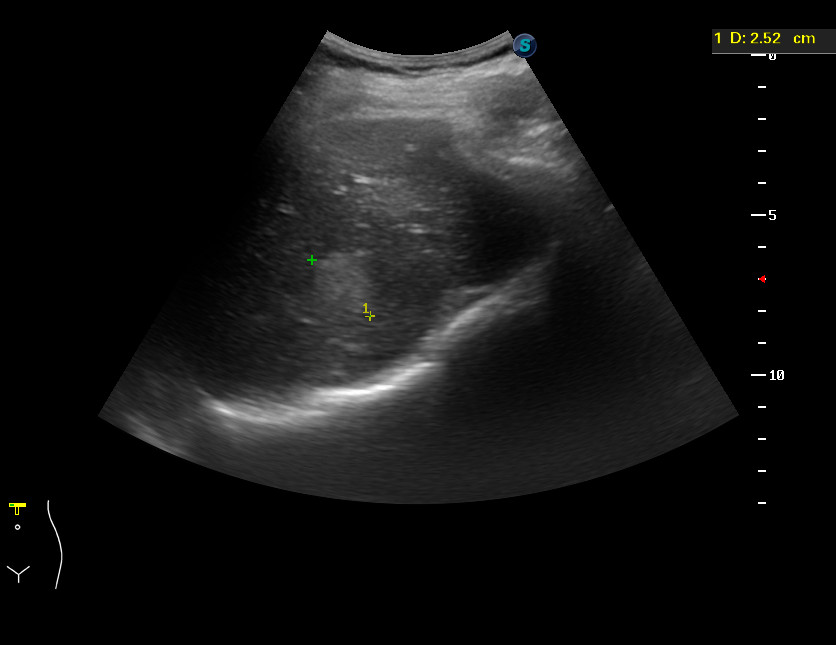

Метастазы ГИСТ в печени. Hepatic GIST Mts

Женщинв 81 год, жалобы на пульсирующее образование в эпигастрии.

С учетом внешнего вида предположена гемангиома больших размеров с разрывом.

Больная прооперирована, выполнена резекция левой доли печени.

Макроскопически - образование на разрезе беловатого цвета, с полостями, заполненными сгустками крови.

Микро: метастаз ГИСТ в печени.